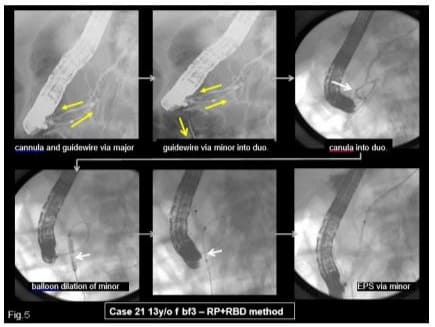

- Reverse Balloon Dilation Method: 13 y/o f bf 3: She entered into our hospital complaining of recurrent epigastralgia. The guidewire, inserted into the major papilla, came out via Wirsung’s duct, connecting branch, Santorini’s duct and minor papilla into the duodenum. The minor papilla was cut by needle type papillotome (rendezvous pre-cut method), then a balloon catheter was inserted along the guidewire and the minor papilla was dilated from the reverse direction by a 4mm dilation balloon, then EPS could be placed into the dorsal duct (Figures 5,6).